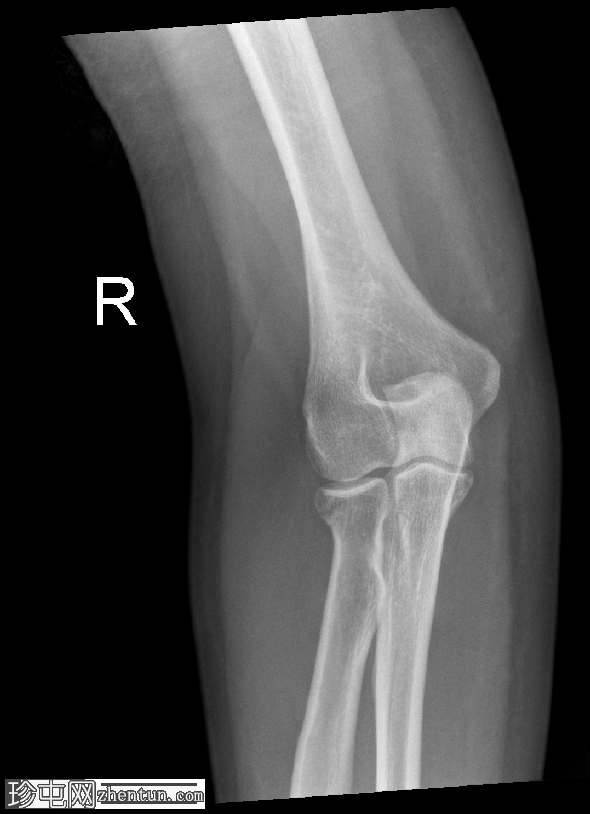

正位

可见桡骨头轻微凹陷性骨折。

桡骨头骨折通常由肘关节伸直时手掌撑地摔倒所致。侧位X线片上前后脂肪垫征的存在是关节囊扩张(由关节积血和关节积液引起)的重要间接指标,即使皮质骨未见明显损伤,也是隐匿性骨折的标志